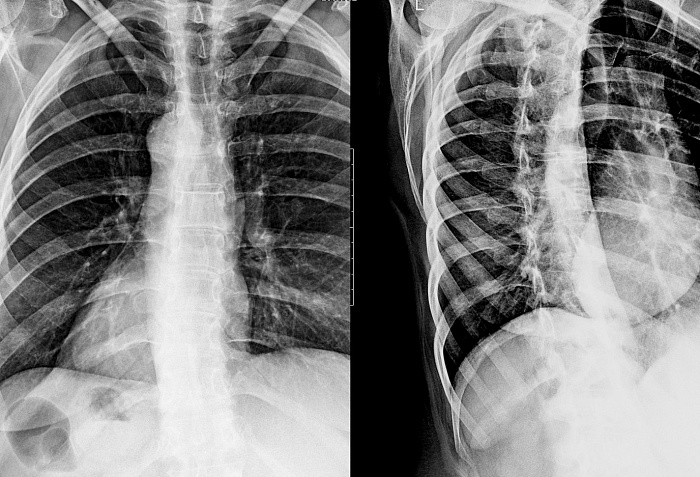

Рентгенография одного отдела позвоночника в косых проекциях – дополнительный вид исследования, который позволяет оценить состояние отдела позвоночника.

Исследование позволяет получить дополнительную информацию по анатомической локализации патологических изменений.